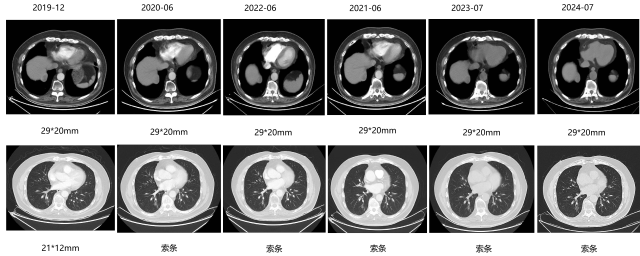

2017-07-25—

二线:CM082+依维莫司

影像学评估—最佳评效 PR

影像学评估